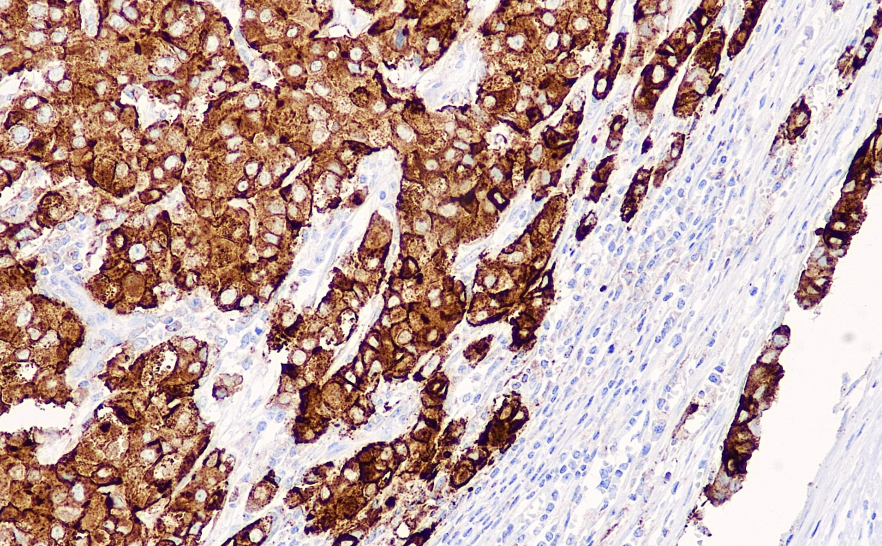

阳性对照: 乳腺癌

EMA是一组糖蛋白,广泛分布于各种上皮细胞及其来源的肿瘤,是许多肿瘤组织的标记物。EMA阳性表达的肿瘤包括大多数癌、间皮瘤、滑膜肉瘤和上皮样肉瘤等,但在肝癌、肾上腺癌,恶性淋巴瘤、黑色素瘤和软组织肿瘤中几乎不表达。

EMA抗体试剂可与EMA分子抗原特异性结合,含EMA抗体试剂的免疫组化试剂盒适用于间皮瘤、滑膜肉瘤和上皮样肉瘤的精准诊断。